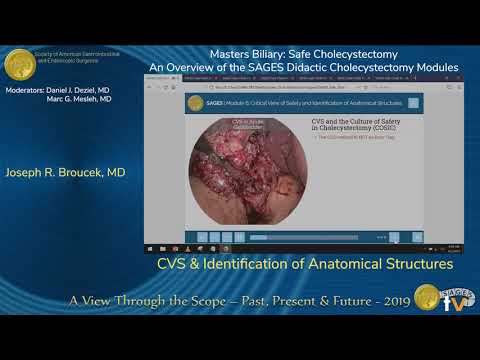

Identificación de estructuras anatómicas - colecistectomía...

Presentado por Joseph R. Broucek en la sesión "Masters Biliary: Safe Cholecystectomy - An Overview of the SAGES Didactic Cholecystectomy Modules" durante la reunión anual de SAGES 2019 en Baltimore, el...